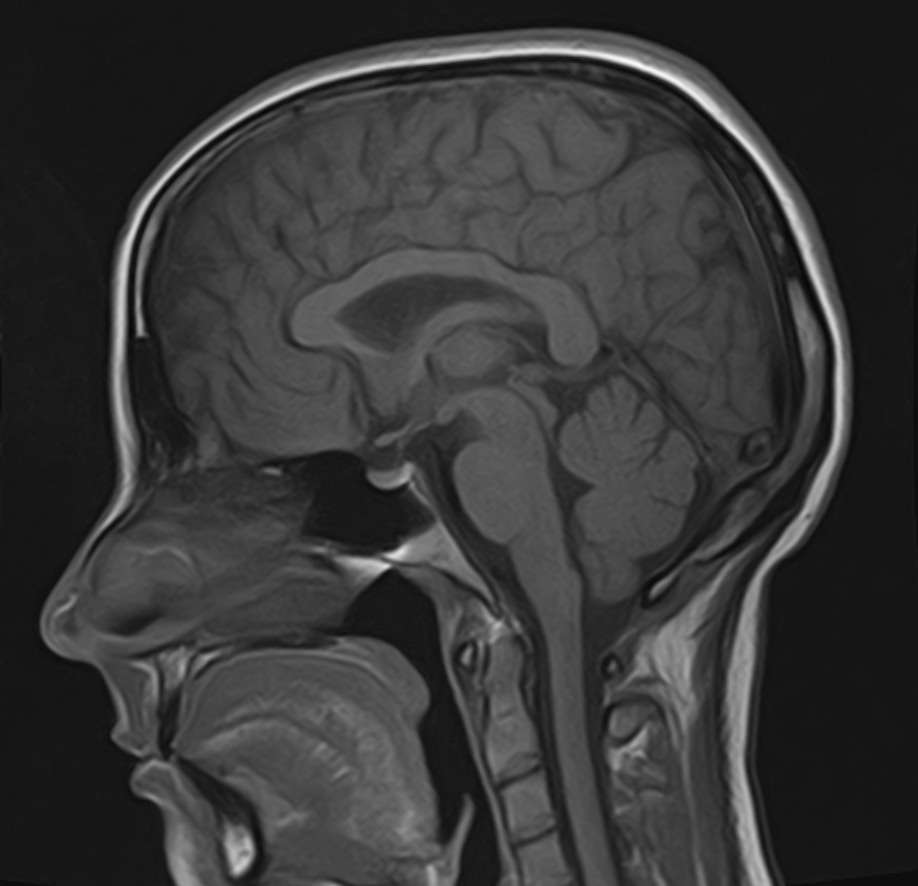

В клинике «Доступная медицина» можно пройти комплексное обследование, включающее в себя два протокола сканирования близко расположенных друг от друга анатомических областей – шейного отдела позвоночника и головного мозга. Метод комплексного обследования оценивает состояние всех структур головного мозга и самого верхнего сегмента позвоночного столба, который включает в себя 7 шейных позвонков, спинной мозг с отходящими от него нервными корешками и окружающими мягкими тканями.

Сканирование проводится на современном высокопольном магнитно-резонансном томографе закрытого типа TOSHIBA VANTAGE TITAN 1,5 Тесла. Магнитно-резонансный томограф производит послойное сканирование исследуемой зоны в разных плоскостях, затем при помощи компьютерных программ преобразует полученные данные в трехмерные изображения с высокой степенью детализации.

Что показывает МРТ головного мозга + шейного отдела позвоночника

В рамках проведения данного комплексного исследования можно выявить:

• очаги ишемического и геморрагического инсульта, область поражения, признаки отека головного мозга, стадию развития заболевания;

• доброкачественные и злокачественные новообразования, их точную локализацию, стадию развития процесса, проводить динамическое наблюдение за опухолевым процессом на фоне лечения;

• признаки демиелинизирующих заболеваний (рассеянный склероз), выявить очаги поражения миелиновой оболочки нервных волокон, определить стадию заболевания;

• характерные признаки дегенеративных заболеваний головного мозга (болезнь Альцгеймера, старческая деменция, болезнь Паркинсона), определить изменения коры головного мозга и подкорковых структур;

• поражение структур головного мозга на фоне травм, гематомы головного мозга;

• изменения, характерные для психических расстройств различного генеза (эндогенных и экзогенных), после вирусных инфекций, черепно-мозговых травм, отравлений токсическими веществами, на фоне наследственных заболеваний;